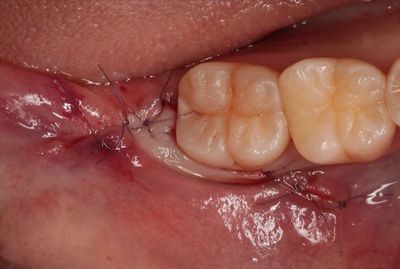

2018.11.24 吸収性の糸で縫合しました。

IMG_8919_R261.JPG